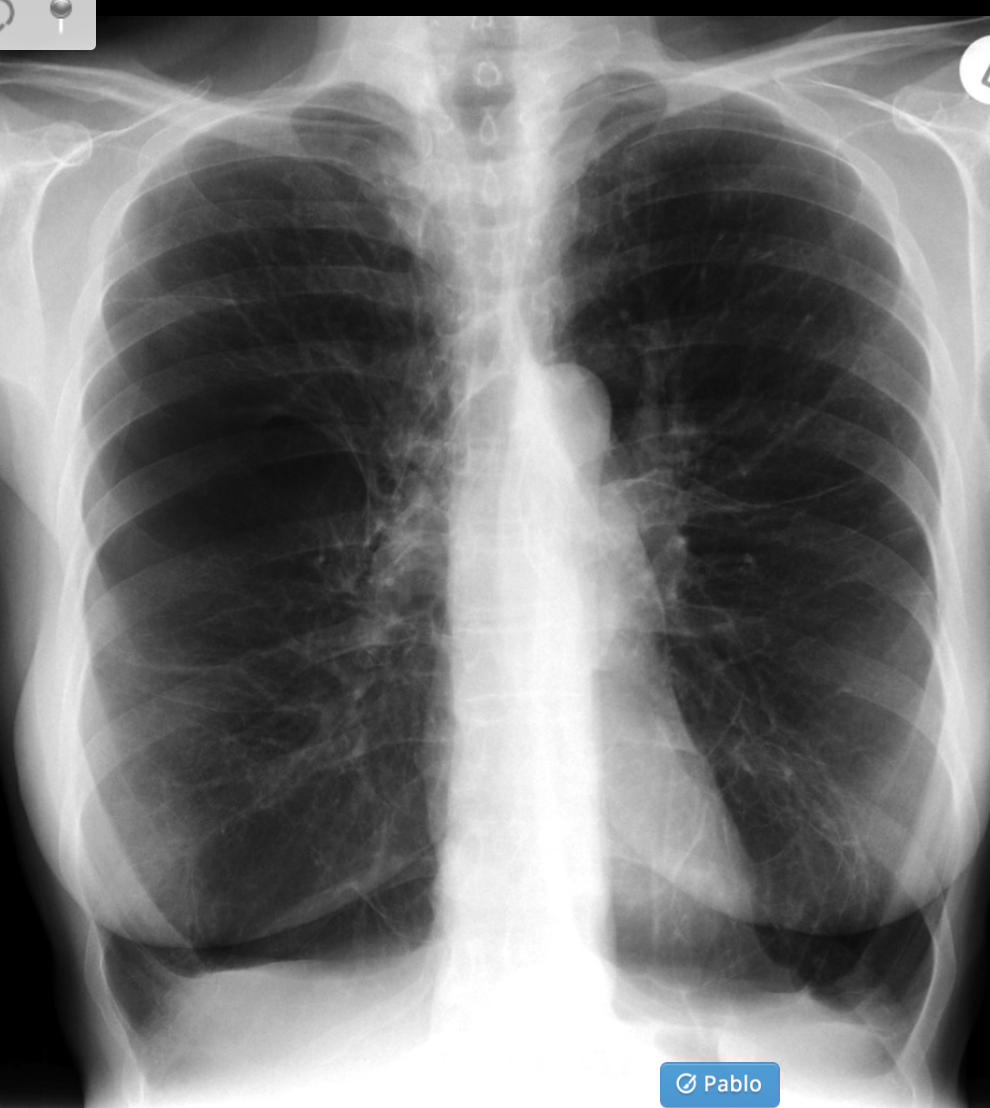

Plain radiograph

Chest radiographs can be normal 2. Abnormalities, if present, are non-specific and include:

cardiomegaly: left atrial enlargement

intracardiac tumoral calcification

evidence of mitral valve obstruction

evidence of elevated left atrial pressure, e.g. pulmonary edema